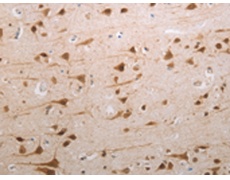

IHC positive control: |

Human brain |